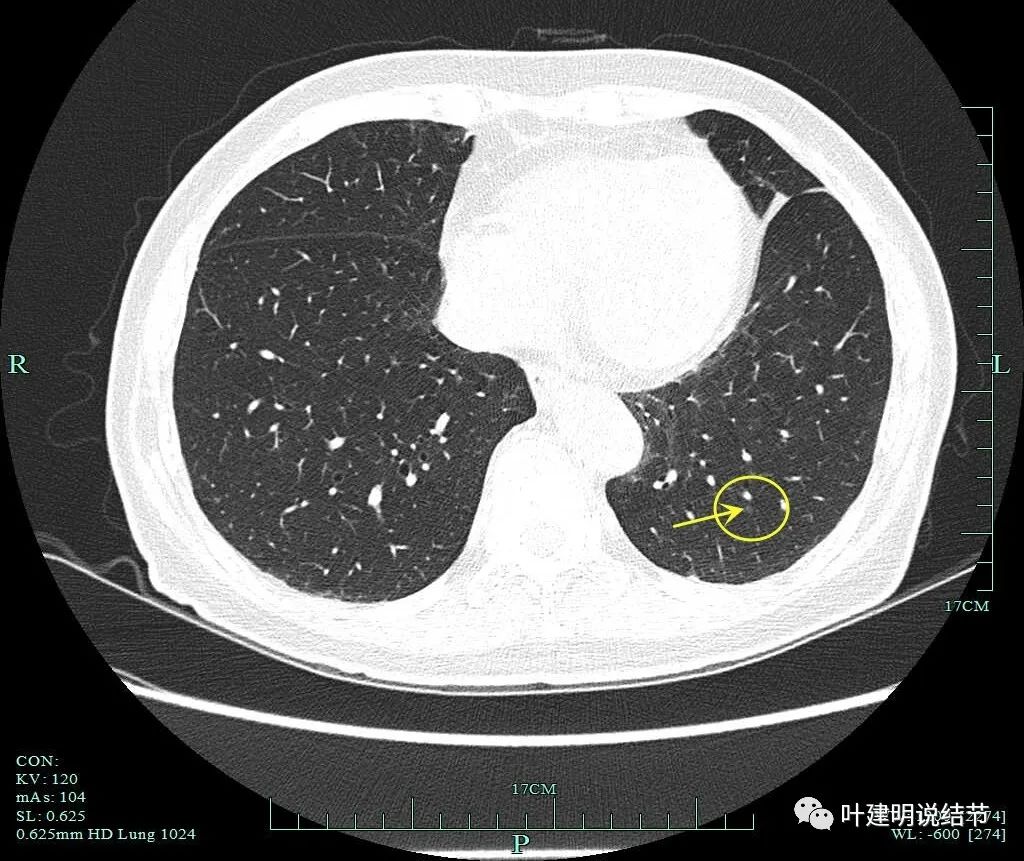

薄层平扫影像:

病灶1:右肺尖淡磨玻璃结节,微小而轮廓较清,考虑肺泡上皮增生可能性大,风险低,能随访。

病灶2:右肺尖淡磨玻璃结节,有微小血管进入,轮廓与瘤肺边界清,从密度看不典型增生可能性大,但因有微血管,升一级考虑,所以有原位癌可能性,近期风险不高,可随访。

病灶3:右肺上叶尖段微小磨玻璃结节,约2毫米,在病灶2附近,考虑肺泡上皮增生可能性大,风险低,能随访。

病灶4:右上叶淡磨玻璃结节,轮廓清,没有实性成分,考虑肺泡上皮增生可能性大。风险低,能随访。

病灶5:右上叶前段淡磨玻璃结节,密度低,轮廓清,边缘毛糙,考虑不典型增生可能性较大,风险不算大,能随访。

病灶6:右上叶后段混合磨玻璃结节,实性成分少,总体密度不高,但轮廓清,有血管进入。单凭密度应该原位癌或不典型增生,但因血管征存在升一级考虑,微浸润性腺癌不能除外。有一定风险性,可考虑干预切除或4-6个月复查随访。

病灶7:右肺靠心缘侧微小纯磨玻璃结节,考虑肺泡上皮增生可能性大些,风险低,能随访。

病灶8:右下叶磨玻璃结节了,轮廓清,血管贴边,边缘显毛糙。

有明显小血管进入,小血管有异常增粗。从密度考虑不典型增生可能性大,但因血管进入升一级考虑,原位癌可能性大点。如果没有上叶病灶6存在,此灶可随访,近期风险不算高。

病灶9:右中叶实性结节,密度过高,小而实的结节以良性可能性大。

病灶10:左上叶微小磨玻璃结节,似见微小血管进入,边缘略模糊,考虑肺泡上皮增生或不典型增生可能性大,位置不好,靠肺门较近,难以楔形切除,可先随访。

病灶11:左肺下叶微小磨玻璃结节,肺泡上皮增生可能性大,风险低,可随访。

两肺多发磨玻璃结节,除了病灶6有些许偏实性成分以及病灶9考虑为实性结节以外,均仍属纯磨玻璃密度,虽然多为肿瘤范畴的,具体判断如前所述。但许多病灶都还很小,风险不大,反正又多,都切光既不大可能,也没有意义。目前只需要考虑处理有一定风险的结节,而且尽量要少切肺组织,为以后其余结节若进展留足余地。最危险的是病灶6,因为混合磨玻璃密度伴血管进入与穿行;其次是右下叶病灶8,虽纯磨,但有血管异常增粗并进入;再次之是病灶2,密度低,但它相对较大,也有微血管征。